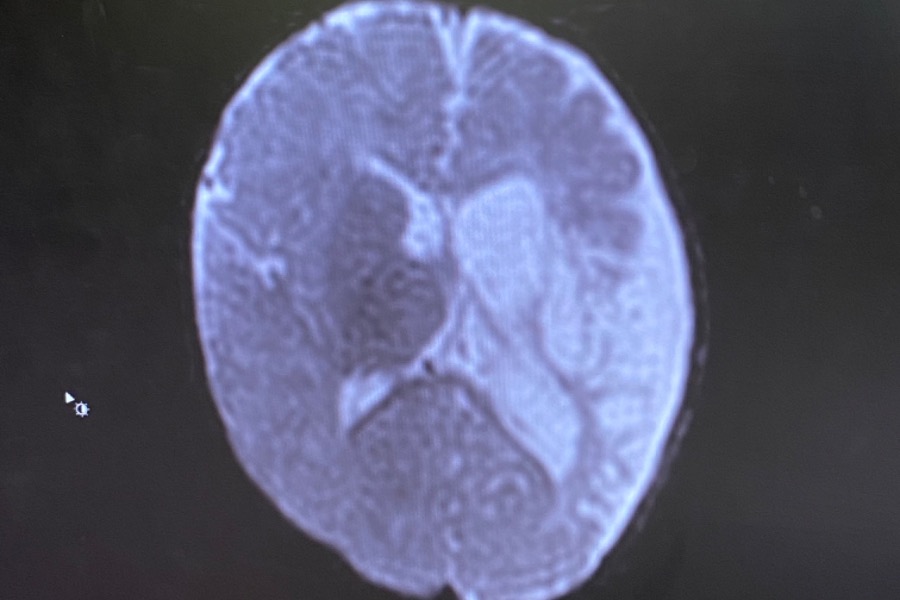

Our son, Caleb was diagnosed with Cerebral Palsy caused by a brain bleed. In the image below the white areas on the right side of the image are dead parts of the brain.

The extent of the bleed this much greater than initially thought, and as a result Caleb can’t properly use his right hand. It is also likely he will walk with a limp. Whether or not the other portion of his brain can compensate for the language center which is affected as well is unknown. There is also, of course, concern about psychological impacts of teased / physically different.